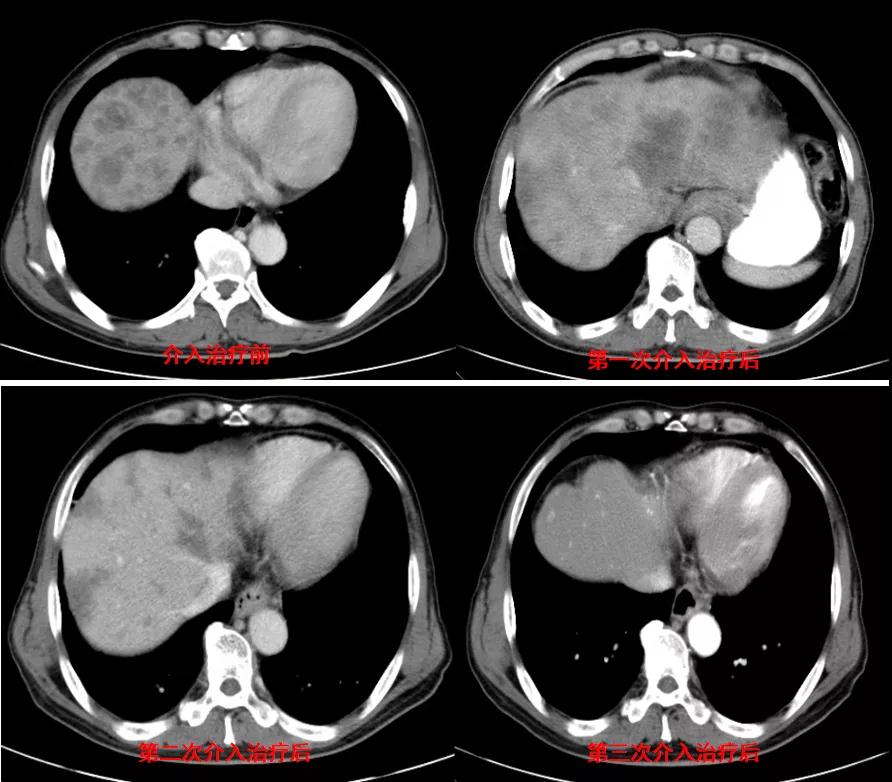

诊治经过:2021年5月16日患者行第三次经皮动脉化疗灌注栓塞术(铂类+氟尿嘧啶)治疗,并继续联合吡咯替尼治疗。结果见图4。

图4

总结:本例患者为胃癌IV期,伴肝转移及淋巴结转移,经介入联合吡咯替尼治疗后,肝转移灶显著缩小。治疗前肿瘤标志为:癌胚抗原3574.3ng/ml、CA12-5 650U/ml、CA19-9 1212U/ml、CA15-3 333U/ml;治疗后肿瘤标志为:癌胚抗原7.6ng/ml、CA12-5 12.8U/ml、CA19-9 17.4U/ml、CA15-3 6.7U/ml。治疗后,肿瘤标志物显著降低,且腹部CT结果显示该患者肝转移病灶较治疗前明显减少。患者目前带瘤总生存达10个月,病情稳定。